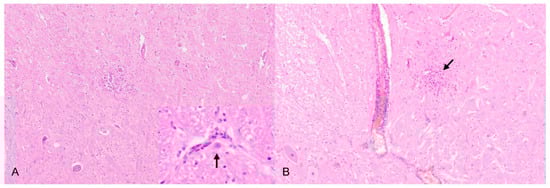

Like mice, rats are infectable by different inoculation routes [115,116,122] and show similar clinical signs. Diarrhea as well as orchitis are reported for male rats [115]. After intramuscular injection PRV can be isolated from the inoculation site, kidney and brain. Nonsuppurative encephalitis, perivascular cuffing in the grey and white matter, slight neuronal necrosis of mitral and tufted cell layers in the olfactory bulb and few intranuclear inclusion bodies are present in rats infected orally, subcutaneously and intranasally. Endothelial hypertrophy also occurs, but these lesions are not attributable to a certain inoculation route [116]. After intraperitoneal injection, PRV antigen is detectable in the peritoneum, myenteric and submucous plexus, abdominal sympathetic and mesenteric ganglia, dorsal root ganglia, spinal cord and adrenal gland [117]. Intraocularly infected rats have been mainly used in PRV research as a well-characterized model of PRV infection [122,123,124]. In this model, viral antigen can be reproducibly detected in retinal ganglia as well as in the cerebrum, midbrain and superior cervical ganglia.

PRV in guinea pigs has not been studied intensively. Guinea pigs can be infected via the intramuscular and intranasal routes [125]. The animals show fever and display severe pruritus, self-mutilation and neurologic deficits such as paresis and epileptiform convulsions. Histopathologically, necrosis of neurons in the olfactory bulb and occasionally in the cerebral cortex, hippocampus, midbrain and brainstem are observable. Intranuclear inclusion bodies are only occasionally seen. Few foci of microgliosis as well as perivascular cuffing mainly consisting of lymphocytes and macrophages appear in affected brain areas.